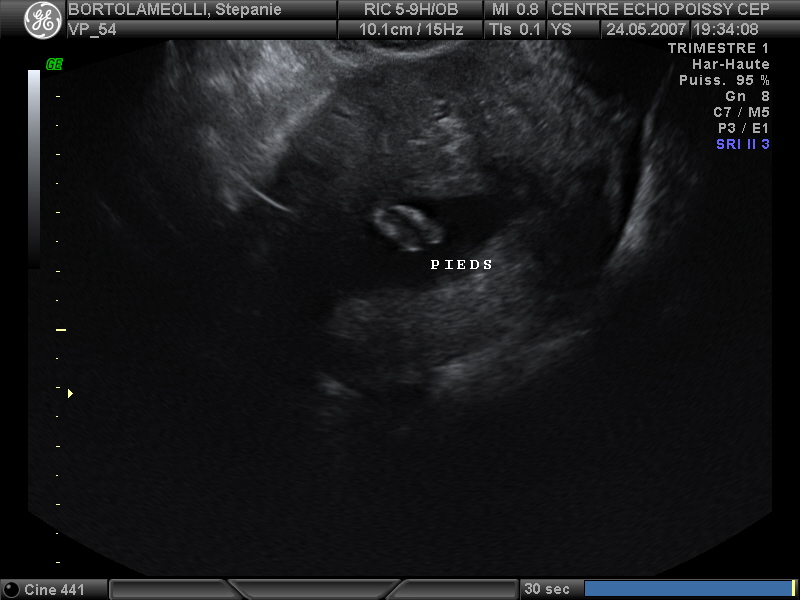

Echographies

Mai 2007